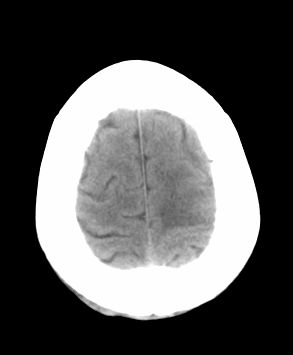

男 42岁 头痛20天

左顶叶见片状低密度影,边界不清,内见斑片状等密度影。考虑转移性肿瘤可能性大,建议ct增强或mr增强扫描。建议胸部检查,排除肺部病变。

左顶叶见片状低密度影,内似见结节状略高密度影,建议增强扫描。

左侧顶叶低密度灶,性质待定;建议行ct增强扫描或mri检查。

左顶叶见片状低密度影,边界不清,内见斑片状等密度影。考虑转移性肿瘤可能性大,建议ct增强或mr增强扫描。建议胸部检查,排除肺部周围型腺癌。

左侧顶叶低密度灶,性质?建议行ct增强扫描或mri检查。

左侧顶叶低密度灶,胶质瘤或转移瘤,建议ct增强扫描或mri检查。